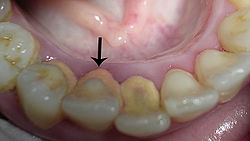

Tandsteen ontstaat doordat het calcium en fosfaat in het speeksel in de tandplaque gaat zitten. Die tandplaque verhardt zich dus. Er zijn twee soorten tandsteen: subgingivaal en supragingivaal tandsteen. Subgingivaal tandsteen is tandsteen dat onder het tandvlees zit. Supragingivaal tandsteen zit boven het tandvlees op de tand of kies.

Tandsteen ontstaat het snelst bij de uitgang van speekselklieren, bijvoorbeeld vlak achter de ondertanden.